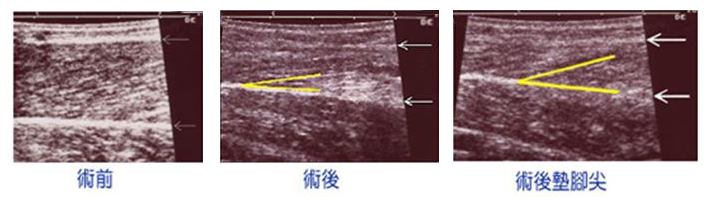

我們就下病例加以解釋。病例術前的小腿圍是33公分,拿掉部份內腓、外腓及比目魚肌後二個半月,小腿圍縮減為29.5公分。

術前的內腓厚度是19 mm(超音波左圖,白色箭頭內為內腓)。術後二個半月的內腓厚度是11 mm(超音波中圖)。肌肉在超音波下可以看到紋理,當肌肉在收縮時肌肉紋理的角度會變大。病人在術後腳板平放時內腓肌肉紋理是12度(超音波對中圖,黃色間的角度),術後墊腳尖時變為20度(超音波右圖),可見術後的肌肉是有功能的。但如果肌肉部份切除的量較多的話,肌肉功能也可能會受影響。